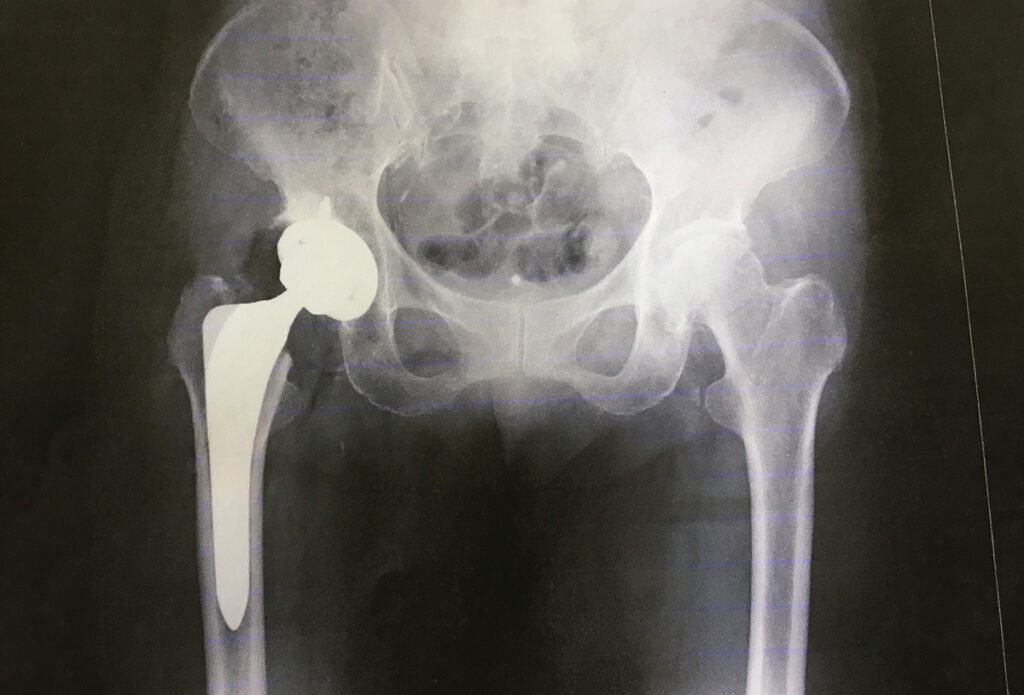

やはり、びっこが続き、痛みが増し、とある病院に再度診察へ行ってみると、先生が「今度は膝ではなく股関節をレントゲン撮ってみましょう」と撮ってみたところ、ペルテス病と診断されました。

小学校1年生から6年生まで入園しました。退園する時、小さかったので鮮明には覚えていないのですが、先生が「つよし君の股関節は右と左、形が違うからね。少しつぶれて治ったからね」、そんなことをおっしゃっていたかと思います。

これは明らかにおかしいと最寄りの整形外科で診てもらったところ、変形性股関節症と診断されました。何か所かの病院を渡り歩き、令和5年11月20日に人工股関節置換術を受けることになりました。→ここからのエピソードは闘病日記を参照してください。

わたしの股関節状態は、先生がおっしゃるには「すぐに対処しないといけない末期の状態」だったそうです。

保存療法はあり得ず、手術するしか選択肢のない待った無しの状態でした。なので、人工股関節手術を受けることに躊躇することはありませんでした。比較的、手術を受けるには若い年齢(手術時49歳)だったそうですが、人工股関節手術が目覚ましい進歩を遂げ、著しく長期耐用性が向上しているという情報が手術することに決めたことの後押しになりました。